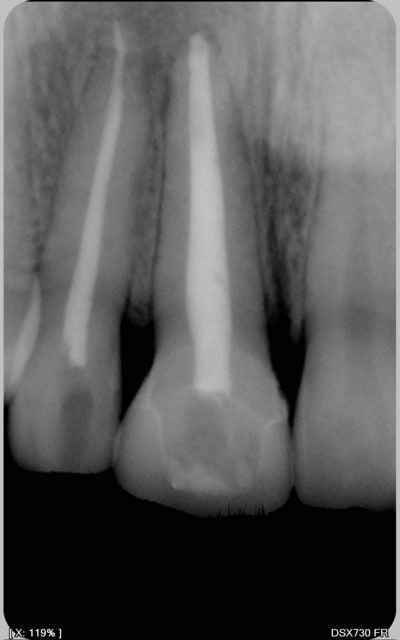

voila quelques traitements,modestes mais je suis encore jeune....

encore des radios,peut-etre assez moyen comme traitement...mais je vu pire...

Cher confrère roumain , tu as sans doute remarqué que lorsque tu réalises de superbes endos sur molaires ( félicitations au vue des radios) tu es rémunéré généreusement par ton patient un peu plus de 80 euros le traitement complet .

Comme tu as pu le constater dans ton beau pays, les soins conservateurs qui représentent 70% de notre activité journalière sont au bas mot remboursé le double , triple voir le quadruple en l'occurrence pour une bio sur molaire ( 100 euros le canal sur certains sites qui font leur pub sur Eugénol ).